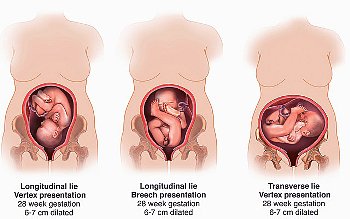

Сідничне передлежання плода

Сідничне передлежання: причини, лікування, пологи

Це не впливає негативно на перебіг вагітності, але значно ускладнює хід пологів, підвищує ймовірність родових травм у плода і матері. У тому ж випадку, коли дитина з'являється на світ головкою вперед, все проходить набагато простіше, і ускладнення виникають рідше.

Побачити положення плода можна на будь-якому терміні вагітності за допомогою УЗД. Але діагностичну цінність дане дослідження в цьому випадку має тільки з третього триместру вагітності, так як раніше цього терміну плід може регулярно змінювати своє положення. Таким чином, сідничне передлежання плода в 20 тижнів і навіть в 30 тижнів не повинно викликати ніякого занепокоєння: дитина поки ще зовсім маленький і може вільно переміщатися.

Якщо жінці в ув'язненні УЗД на 32 тижні написали сідничне передлежання, необхідно вжити заходів для перевороту дитини і регулярно перевіряти, чи дали ці заходи позитивний результат. І для цього зовсім необов'язково з чіткою періодичністю проходити ультразвукове дослідження: визначити передлежачої частини гінеколог може і методом пальпації. Для жінки, яка стала на облік у зв'язку з вагітністю, це така ж звичайна процедура, як і регулярні зважування. Лікар пропонує пацієнтці лягти спиною на кушетку і зігнути в колінах ноги, після чого дуже акуратно промацує нижню частину матки. Якщо там виявляється округле утворення, рухоме при вагітності терміном менше 35 тижнів, це і є головка. Якщо ж передлежачої частина не прощупується, дно матки стоїть трохи вище норми, а серцебиття дитини прослуховується вище пупка - лікар може припустити неправильне положення малюка.

Остаточне передлежання дитини найчастіше формується до 35 тижня вагітності. І якщо поки йде 35 тиждень вагітності, тазове передлежання зберігається, необхідно задуматися про заходи, здатних «спонукати» дитини змінити положення свого тіла.

У більшості випадків саме на цьому терміні - після 35 тижнів вагітності формується остаточне передлежання дитини, що визначає його положення щодо матки і родового каналу.

Небезпека тазового передлежання пояснюється, головним чином тим, що пологи в таких випадках бувають дуже травматичні для матері, дитині, в свою чергу, тазове передлежання загрожує асфіксією, тривалим кисневим голодуванням, здатним негативно позначитися на його психічному розвитку.